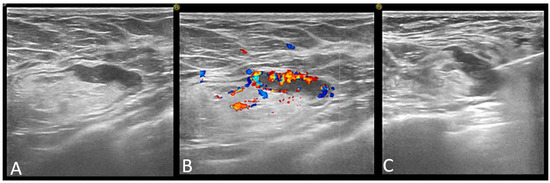

Figure 4. Axillary lymph node classified as abnormal on ultrasound: focal cortical thickening of more than 3 mm (A) with chaotic vessels (B), and core-needle biopsy was performed (C).